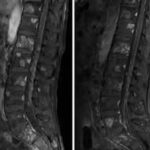

What is an MRI Sacral Spine With Contrast?

MRI Sacral Spine With Contrast is a specialised imaging technique that uses magnetic resonance imaging (MRI) to get detailed images of the lower spine and its surrounding tissue. It is helpful in diagnosing conditions like lower back pain, sciatica, inflammation of the lumbosacral joints, tumours, herniated discs and compressed nerves.